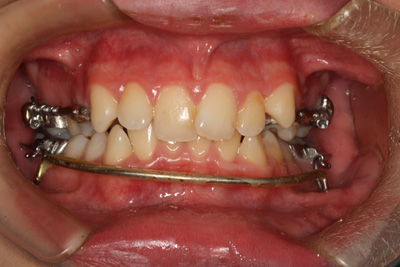

Lip bumper

Lip bumper – to jeden z serii aparatów ortodontycznych pomocny w korekcji wad zgryzu, wad zębowych jak również mający zastosowanie w ortopedycznym leczeniu wad kostnych. Modyfikacja nieprawidłowości zgryzowych następuje poprzez skoordynowaną rozbudowę łuku zębowego dolnego oraz górnego. Umiejętne posługiwanie się tym typem aparatu daje bardzo dobre rezultaty poszerzenia i rozbudowy głównie dolnego łuku zębowego, ale również znajduje zastosowanie do korekcji łuku górnego.

3. Mechanizm działania: dzięki zastosowaniu łuku wargowego z akrylowymi tarczkami, zaburza równowagę mięśniową i umożliwia rozbudowę łuku poprzez działanie języka. Ponadto umożliwia dotylną ekspansję łuku poprzez działanie łuku wargowego.

4. Greenfield Lip Bumper: występuje w dwóch formach – „normalnej” oraz „wysoko-kątowej”; skonstruowany ze stalowego drutu 0.045”, w odcinku przednim z tarczkami i zagięciem w kształcie odwróconej litery V w linii pośrodkowej w celu ominięcia wędzidełka języka oraz bocznie pętli stop o wymiarach 5x5mm odgiętych pod kątem 10o w kierunku policzkowym w dwóch wariantach: